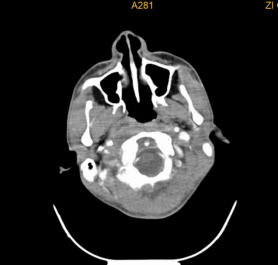

下咽癌颈淋巴结转移

下咽部淋巴组织丰富,较易发生淋巴结转移,早期常转移至同侧颈动脉三角区颈深部淋巴结,多为分化程度较差的癌。而且由于下咽部位置隐蔽,常常原发灶不易发现,还有转移灶很大,原发灶很小的情况。